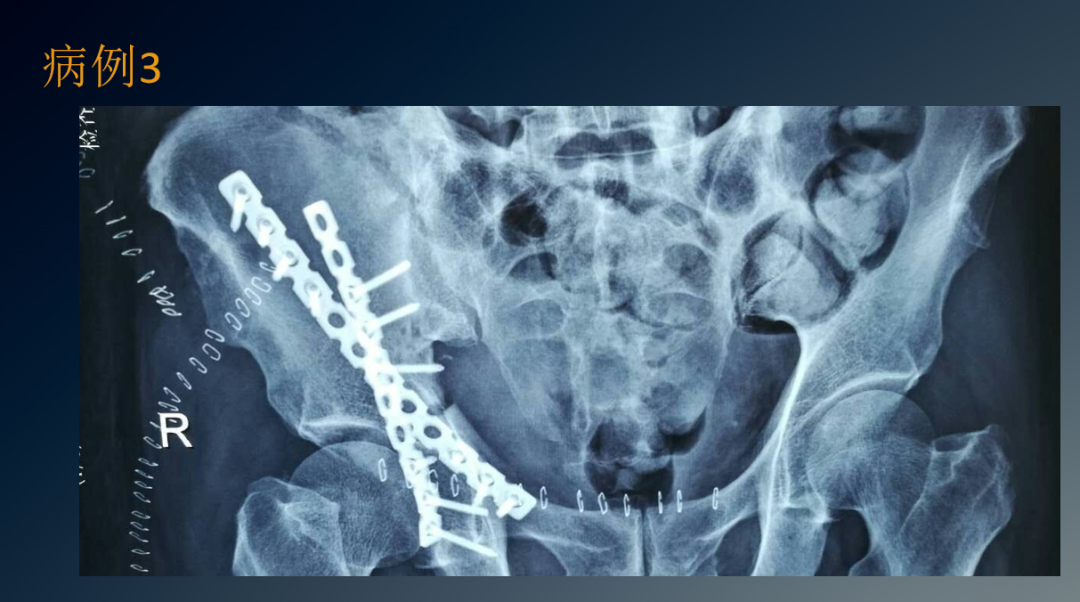

临床病例

治疗盆骨、髋臼骨折常用的手术入路有髂腹股沟入路、K-L入路,前后联合入路,扩大的髂股入路等。髂腹股沟入路主要用于髋臼前壁和前柱骨折,但对于双柱骨折、后壁骨折或累及骶髂关节的髂臼骨折,不建议使用此入路。

K-L入路可直视髋臼后柱的全部侧面,适用于移动的髋臼后柱骨折。扩大的髂股入路对髋臼前柱、关节囊和坐骨大切迹的显露良好,尤其是可显露髋臼顶部的骨折,但因要兼顾前后柱,切口较大,要将臀肌从髂骨上剥离,损伤大出血多。前采用该入路术后出现异位骨化的几率高达85.7%。

因此,该入路目前以较少使用。前后联合入路即K-L入路联合髂腹股沟入路,通过K-L入路可经坐骨小切迹观察四边形区及后柱的骨折复位情况,通过髂腹股沟入路可显露骶髂关节前方,髂骨翼,无名骨,前柱及耻骨联合。采用前后联合入路可减少单一切口所致切口大、肌肉剥离广泛,易损伤血管神经等弊端,可明显减少对髂关节后方组织的干扰,降低异位骨化的发生几率。